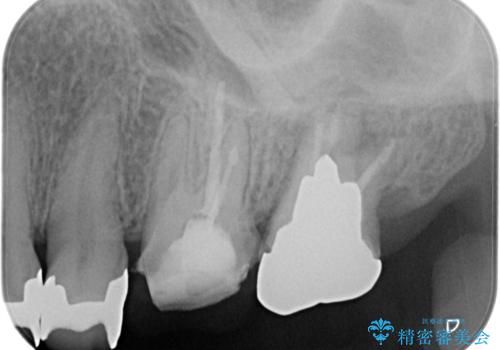

【根管治療】未処置根管を有した歯の再根管治療

- 定期検診にて虫歯を見つけたため、根管治療からオールセラミッククラウンによる修復治療を行いました。

レントゲンにて透過像を認めている上顎第二大臼歯も治療予定です。

上顎第一大臼歯の近心根にはほとんどの場合、神経の管が二本あることが多いです。顕微鏡を用いることで見逃すことなく治療が行えました。